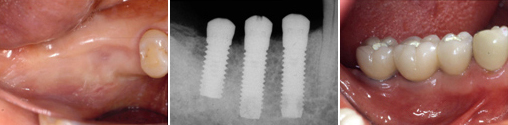

왼쪽 중절치가 더 이상 유지되기 어려울 만큼 나빠졌습니다. → 조심스럽게 해당 치아를 뺀 다음, → 임플란트를 매식합니다

치조골이 건강하고 튼튼한 경우에는 수술직후에 바로 임시치아를 제작할 수 있습니다. → 수술 직후에도 자연스러운 치아의 모습을 유지할 수 있습니다